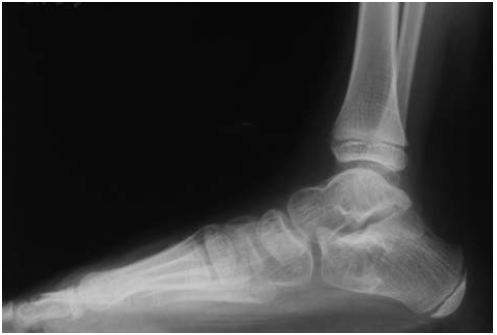

Больная Б., 5 лет, с диагнозом: «ДЦП. Спастическая диплегия. Эквино-плано-вальгусные деформации стоп». Операция — корригирующая остеотомия пяточной кости и пересечение сухожилия икроножной мышцы (рис. 4, 5).

Рис. 5. Рентгенограмма правой стопы через 1 год 7 месяцев после операции